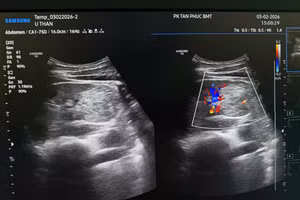

GD&TĐ - Một người đàn ông ở Lâm Đồng, đến khám định kỳ tại Phòng khám đa khoa Tân Phúc Buôn Ma Thuột (Đắk Lắk) thì phát hiện bị ung thư thận.